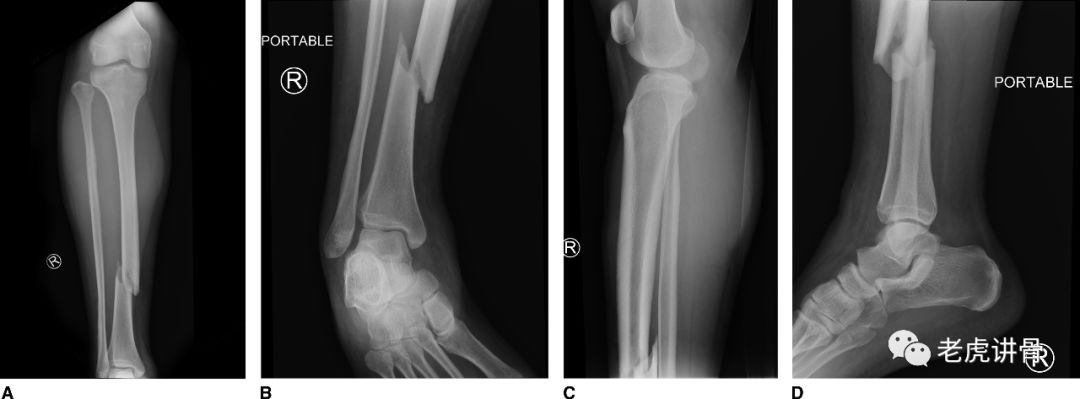

胫腓骨骨折 A 医学百科